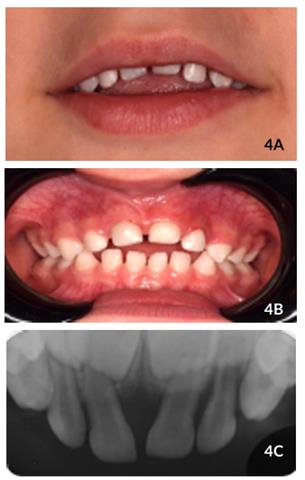

Ao exame clínico após 7 dias, foram observados vermelhidão e inchaço da mucosa adjacente. Não houve mobilidade dos dentes #61 e #62, e o dente #61 apresentava um terço de coroa visível. Ao exame clínico e radiográfico após duas semanas, foi possível observar leve reerupção dos elementos dentários envolvidos (Figuras 3A e 4B).

Figuras 3A y 3B Aspectos clínicos e radiográficos após 2 semanas de acompanhamento ilustrando o início do processo de reerupção dentária.

Após 60 dias, o dente #61 apresentava se com a coroa próxima de estar totalmente visível, enquanto o dente #62 apresentava-se totalmente reerupcionado (Figuras 4A e 4B), sem alterações de cor, queixas de sintomatologia dolorosa, inflamação ou fístula. Além disso, as gengivas apresentavam aspecto saudável. Radiograficamente, não há presença de lesões periapicais e periodontais

Figuras 4A, 4B y 4C Aspectos clínicos e radiográficos após 2 meses de acompanhamento ilustrando a reerupção dentária completa.

(Figura 4C). Ao acompanhamento de 8 meses, constatou-se que o dente #61 reerupcionou satisfatoriamente apesar de estar ligeiramente acima da linha de oclusão e o paciente apresentar mordida aberta anterior. Novamente, foram observados ausência de inflamação gengival, fístula ou sintomatologia dolorosa (Figura 5A). Além disso, em relação ao dente #62, observou se acúmulo de biofilme dental, vermelhidão e inchaço na gengiva inserida adjacente, com recessão gengival na região cervical devido à interferência oclusal, mobilidade grau I e reabsorção radicular externa (Figura 5B). Ao exame radiográfico, não há sinais de lesões periapicais e lesões periodontais no dente #61. O paciente estava